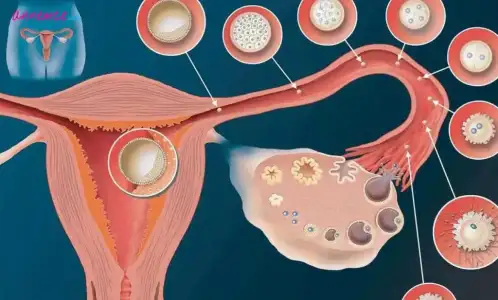

Polikistik Over Sendromu, yumurtalıklarınızın normalden daha büyük ve olgunlaşmamış yumurtalar içeren birçok küçük kistiniz olabileceği anlamına gelir. Bu durumla yaşamak ve Polikistik Over ile hamile kalmak, üreme çağındaki birçok kadın için endişe kaynağıdır.

Polikistik Over Sendromu’nda kistler, yumurtlamayı engelleyen normal miktarlardan daha fazla androjen (erkek cinsiyet hormonları) üretir. Olgun yumurta salınmadığı için yumurtlama gerçekleşmez ve progesteron hormonu yapılmaz. Bu düzensiz veya eksik bir adet döngüsü ile sonuçlanır.

Belirli hormonlar olmadan, yumurtalığınızdaki yumurta tam olarak olgunlaşmaz. Yumurtayı tutan folikül büyümeye devam eder ve sıvı ile dolar. Ancak onu parçalayacak olgun bir yumurta olmadığı için kist olarak kalır.Polikistik Over Sendromu’nda kistler, yumurtlamayı engelleyen normal miktarlardan daha fazla androjen (erkek cinsiyet hormonları) üretir. Olgun yumurta salınmadığı için yumurtlama gerçekleşmez ve progesteron hormonu yapılmaz. Bu düzensiz veya eksik bir adet döngüsü ile sonuçlanır.

Temel olarak, PCOS vücudunuzun anormal düzeyde androjen (erkek hormonları) üretmesine neden olur. Androjenler, erkek cinsiyet organlarının ve diğer erkek özelliklerinin gelişiminde önemlidir. Ancak, kadınlarda androjenler genellikle östrojene dönüştürülür.

Yüksek androjen seviyeleri yumurtalarınızın gelişimini ve yumurtalarınızın düzenli salınımını engeller. Sağlıklı bir yumurta bırakılmazsa, erkekten gelen spermler tarafından döllenemez, yani hamile kalamazsınız.